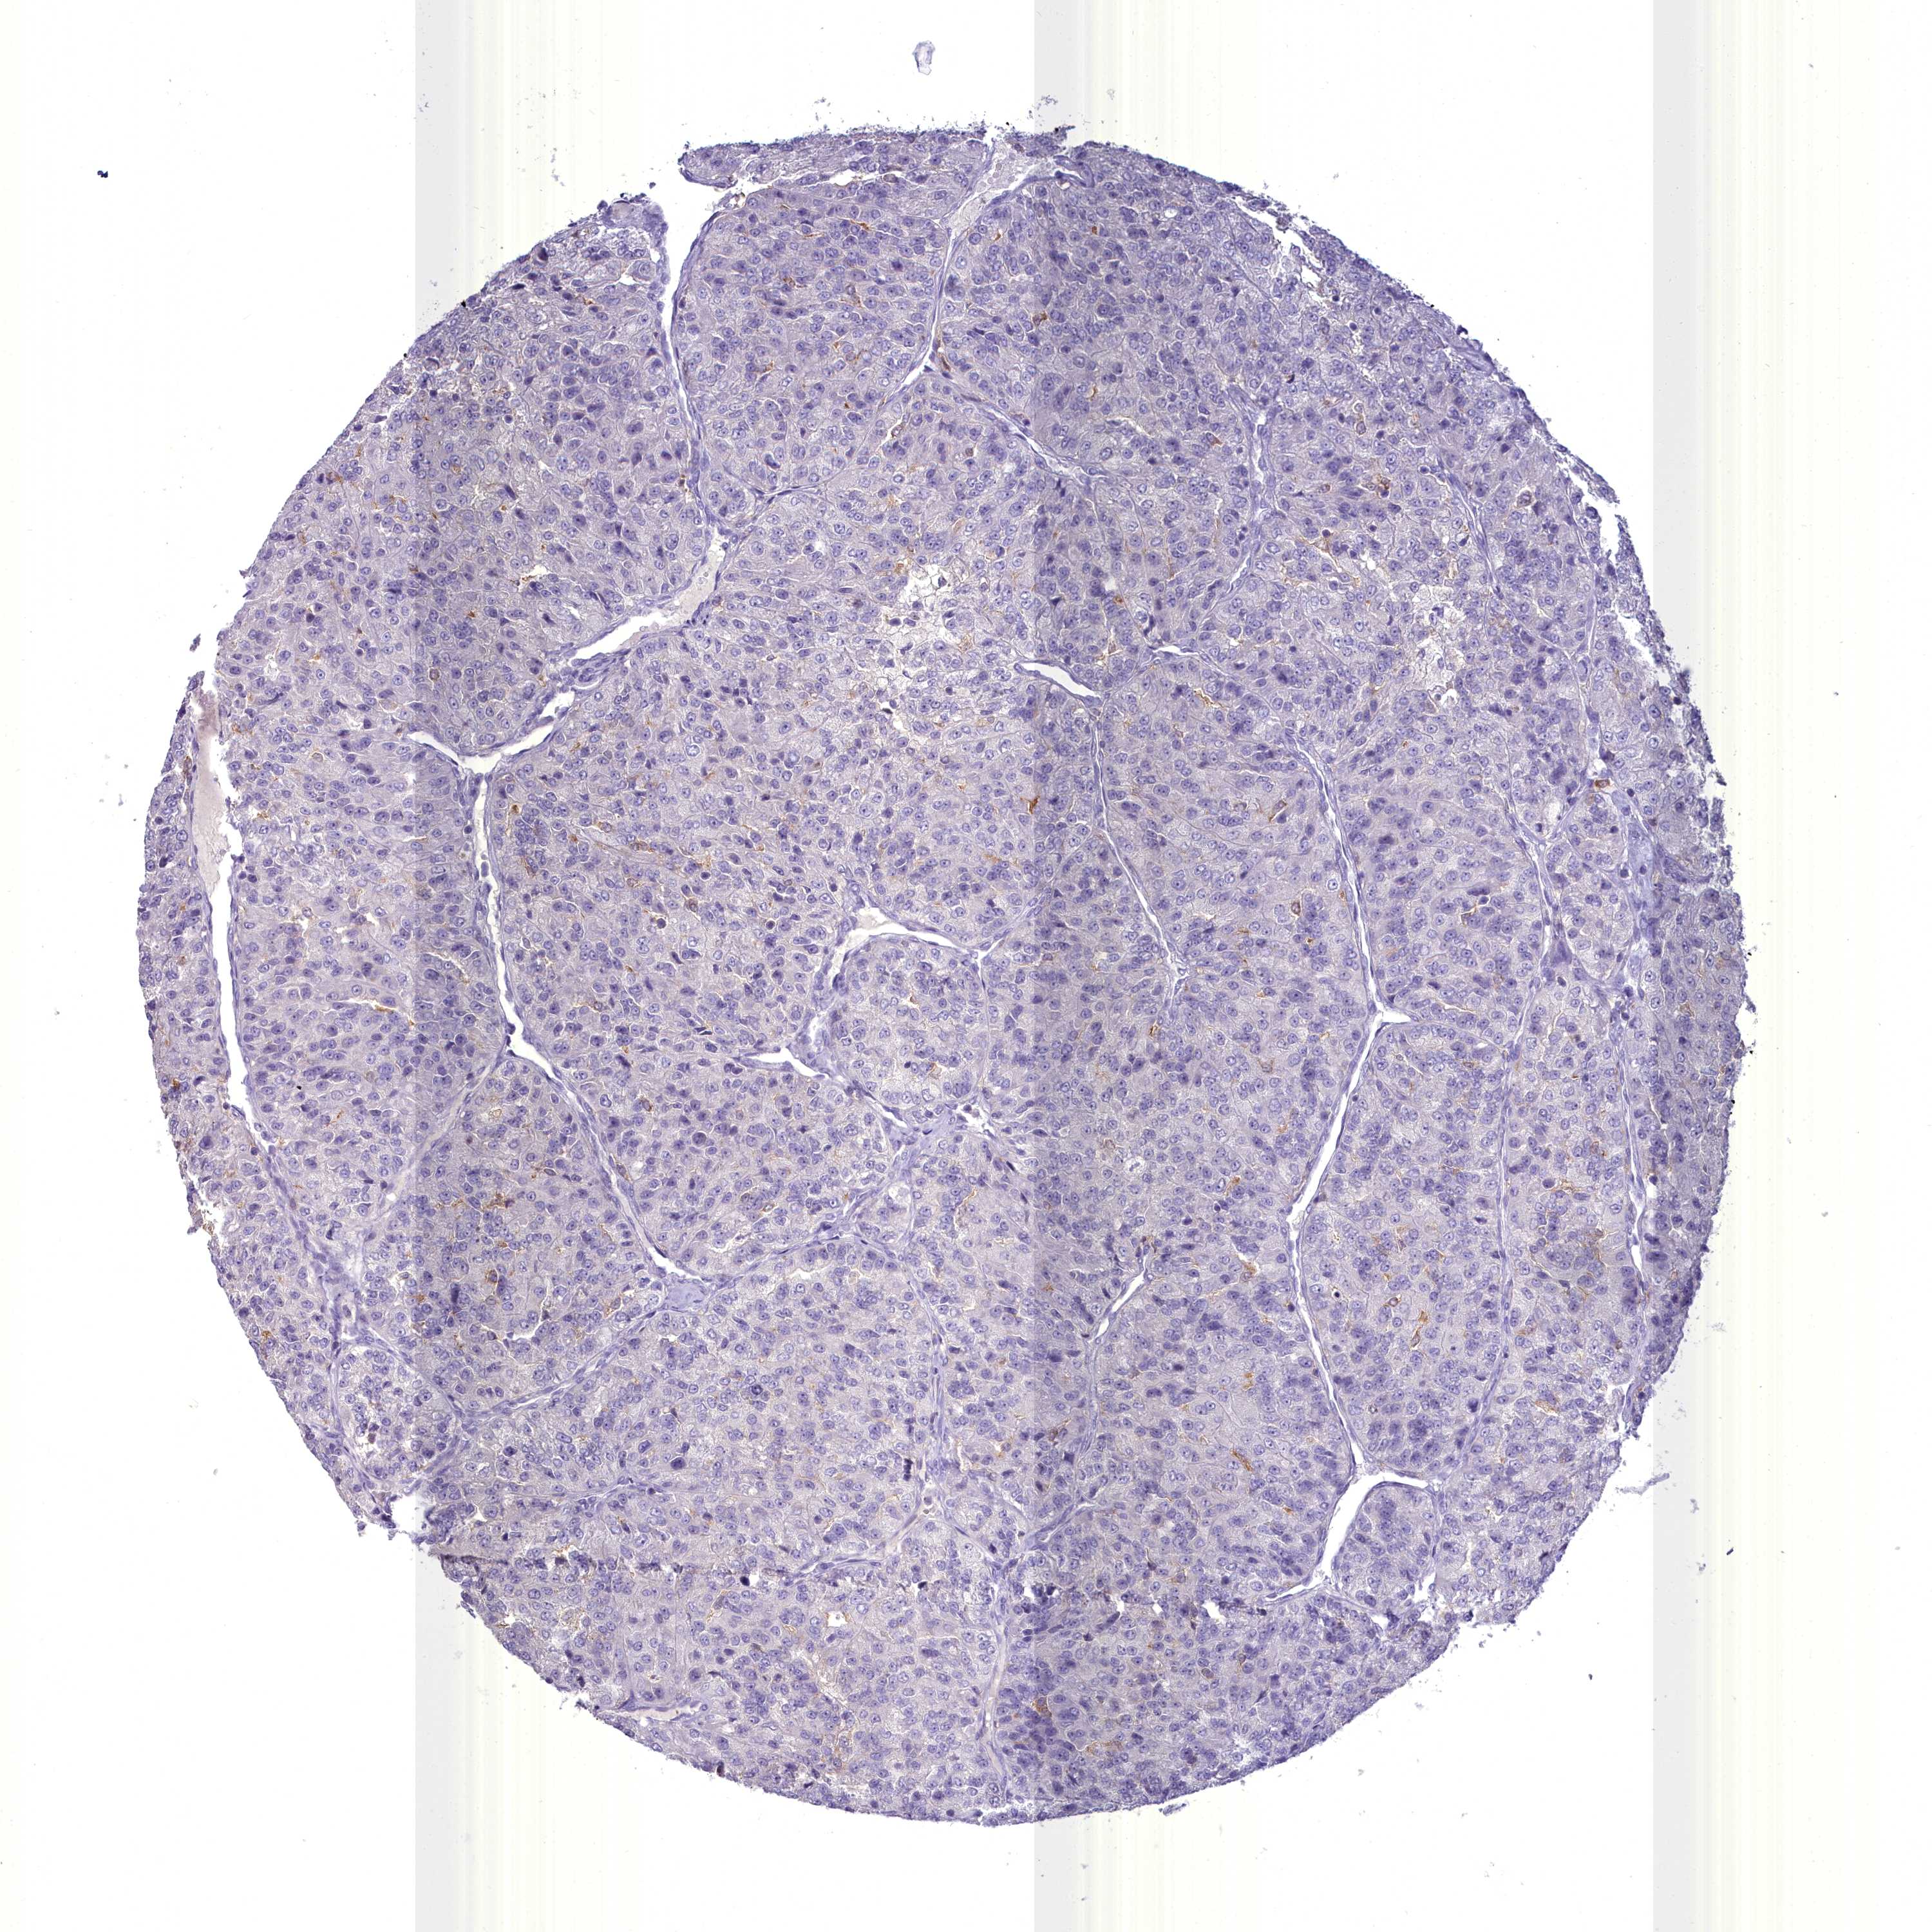

KIDNEY RENAL PAPILLARY CELL CARCINOMA (TCGA) - Interactive survival scatter ploti

BLNK is not prognostic in Kidney Renal Papillary Cell Carcinoma (TCGA)

Best expression cut offi